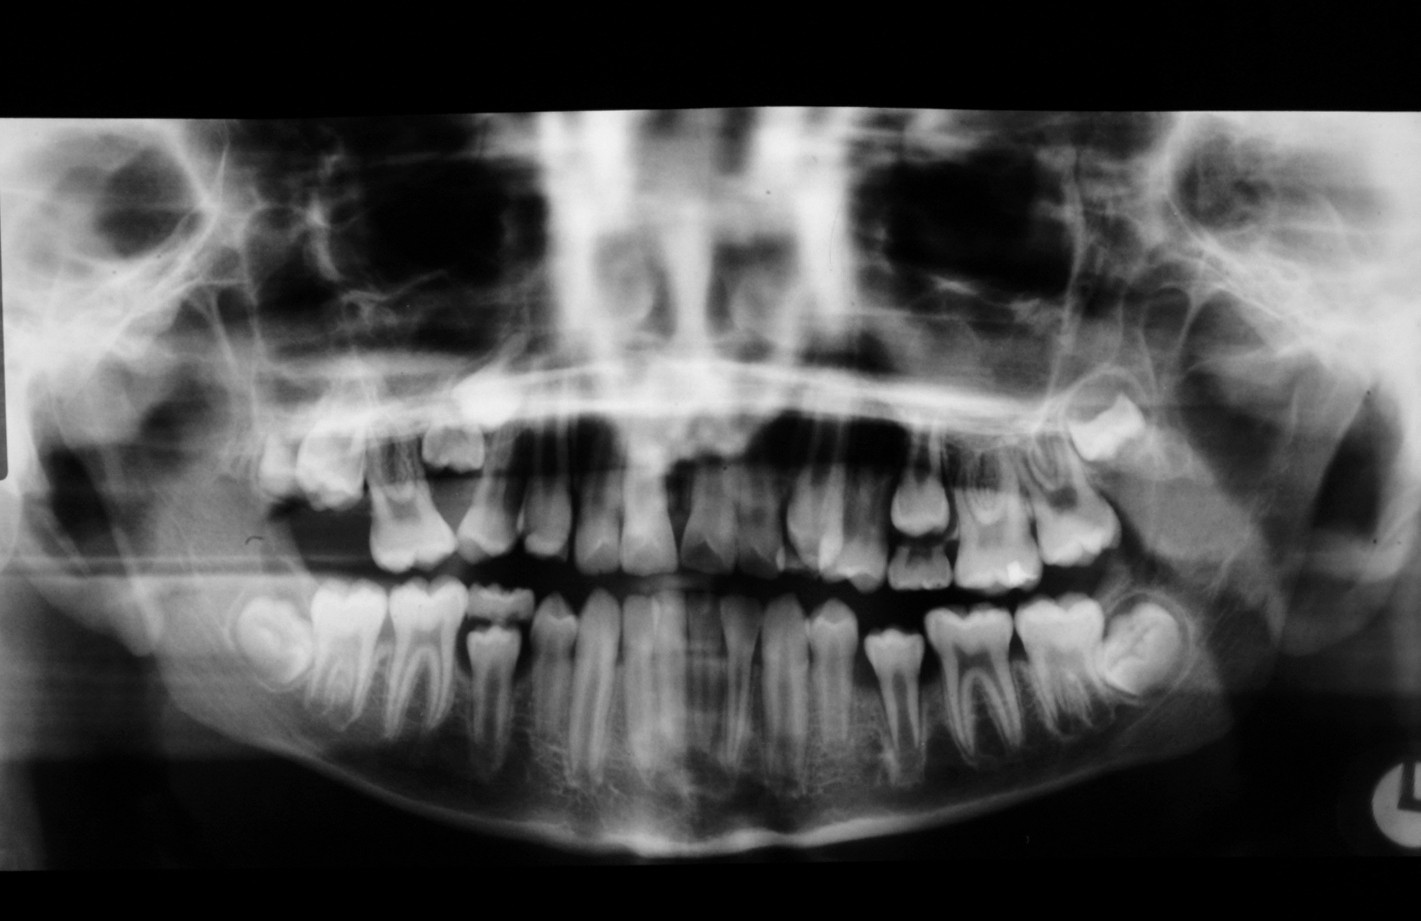

Assessment of the tooth is both clinical and radiographic. If somebody presents in pain, it is important to establish that this is coming from the third molar and not elsewhere. Pain is often vague, poorly localised and may be referred from another tooth, or as part of facial arthromyalgia (condition affecting the jaw joint). A dental panoramic radiograph is ideal as it helps to assess all the teeth at once. The health of the adjacent molars may influence the decision whether to remove the third molar or not. Large crowns or old restorations are all at risk of dislodgement during surgery. It is also worth considering whether alternative treatment options are available. For instance, pericoronitis due to an over-erupted upper third molar may be dealt with by extracting that tooth only, with or without operculectomy. In the presence of other teeth of poor prognosis, will it be better in the long term to save the third molar which may be used as a denture or bridge abutment in the future?

These points help to determine whether the tooth can be simply elevated or will need a surgical approach. A series of radiographs depicted in Figure 4 to Figure 8 illustrate these points further.